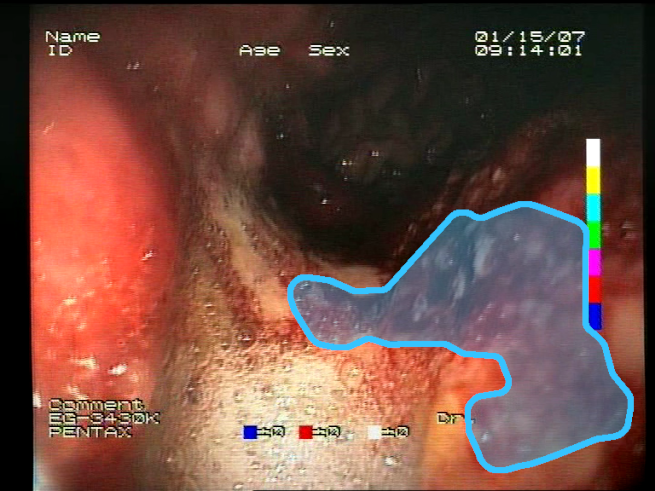

As a result of the design process, nine high-level features (denoted F1–F9) were defined. The features are proposed with simple definitions that also include exemplary images, presented in Table 1. For each image, a blue annotation is presented, illustrating the image regions where the feature is hypothetically present.

Table 1.

Definitions of the nine proposed visual features of endoscopic bleeding. For each image, a blue annotation is presented, which illustrates the area of the image where the feature is hypothetically present.